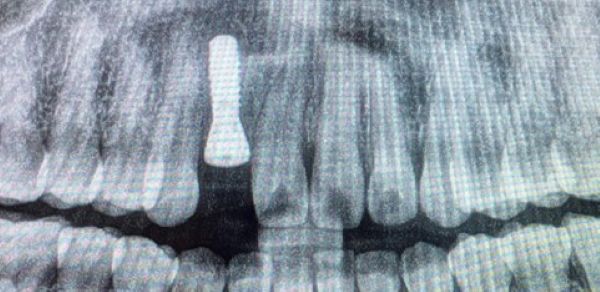

患者様は、元々右上の側切歯(前歯の真ん中の隣にある歯)がなく、乳歯をそのまま使っていましたが、虫歯ができてしまい治療が必要になりました。しかし、乳歯の根が短く、歯自体がグラグラしている状態であり、虫歯治療に耐えられる状態ではありませんでした。

そこで、患者様とご相談したところ、乳歯は抜歯をしてインプラントで治療していくことをご希望されたため、インプラント治療を行う方針で決まりました。

まずは乳歯の抜歯を行い、歯が無くなった所には一時的な仮歯を作成いたしました。

乳歯は、歯根がほとんど吸収して無くなっている状態でしたので、抜歯後の傷口はかなり浅く、抜歯後の痛みもほとんどなかった様です。

今回は、抜歯後の治癒を待つ時間が少なくて済んだため、抜歯後2ヶ月ほどでインプラントを埋入するオペを行いました。

インプラントを埋入し、4ヶ月待ってから上部構造のための歯型とりを行いました。